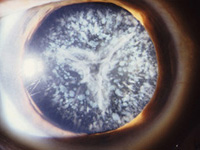

Katarakt (Grauer Star)

Typische Symptome des Grauen Stares sind Sehverschlechterung, Blendempfindlichkeit, eine Verschlechterung des Dämmerungssehvermögens, z.B. beim Autofahren. Weiterhin kann sich die Brillenglasstärke verändern. Die Ursache ist eine Trübung der Augenlinse.

Die einzige Methode, den Grauen Star wirkungsvoll zu behandeln, ist die Katarakt-Operation. Dabei wird die trübe Augenlinse entfernt und durch eine Kunstlinse ersetzt. Die Vorbereitung besteht u.a. aus einer exakten Vermessung des gesamten Auges, der optischen Biometrie, mit dem IOL-Master.